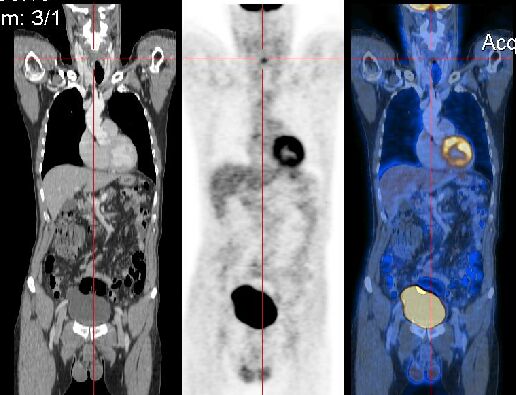

En preklinisk PET/CT-skanner er en liten dyreskanner, som brukes i hovedsak til skanning av mus og rotter. I april 2013 fikk vi en preklinisk PET/CT-skanner i Bergen: nanoScan fra Mediso. Det er plassert på PET-senteret på Haukeland universitetssykehus. Denne skanneren tilhører MIC (Molecular Imaging Center) ved Universitetet i Bergen, og leies ut til bruk i forskjellige forskningsprosjekt.

Kliniske og prekliniske PET/CT-skannere fungerer i prinsippet på samme måte, men vi trenger egne PET/CT-skannere til preklinisk bruk på grunn av størrelsen på dyrene som blir skannet. Her ved Haukeland bruker vi skanneren blant annet til karakterisering av svulster og evaluering av behandlingseffekt: Det gjør vi ved å skanne dyr før, underveis og etter behandlingen.